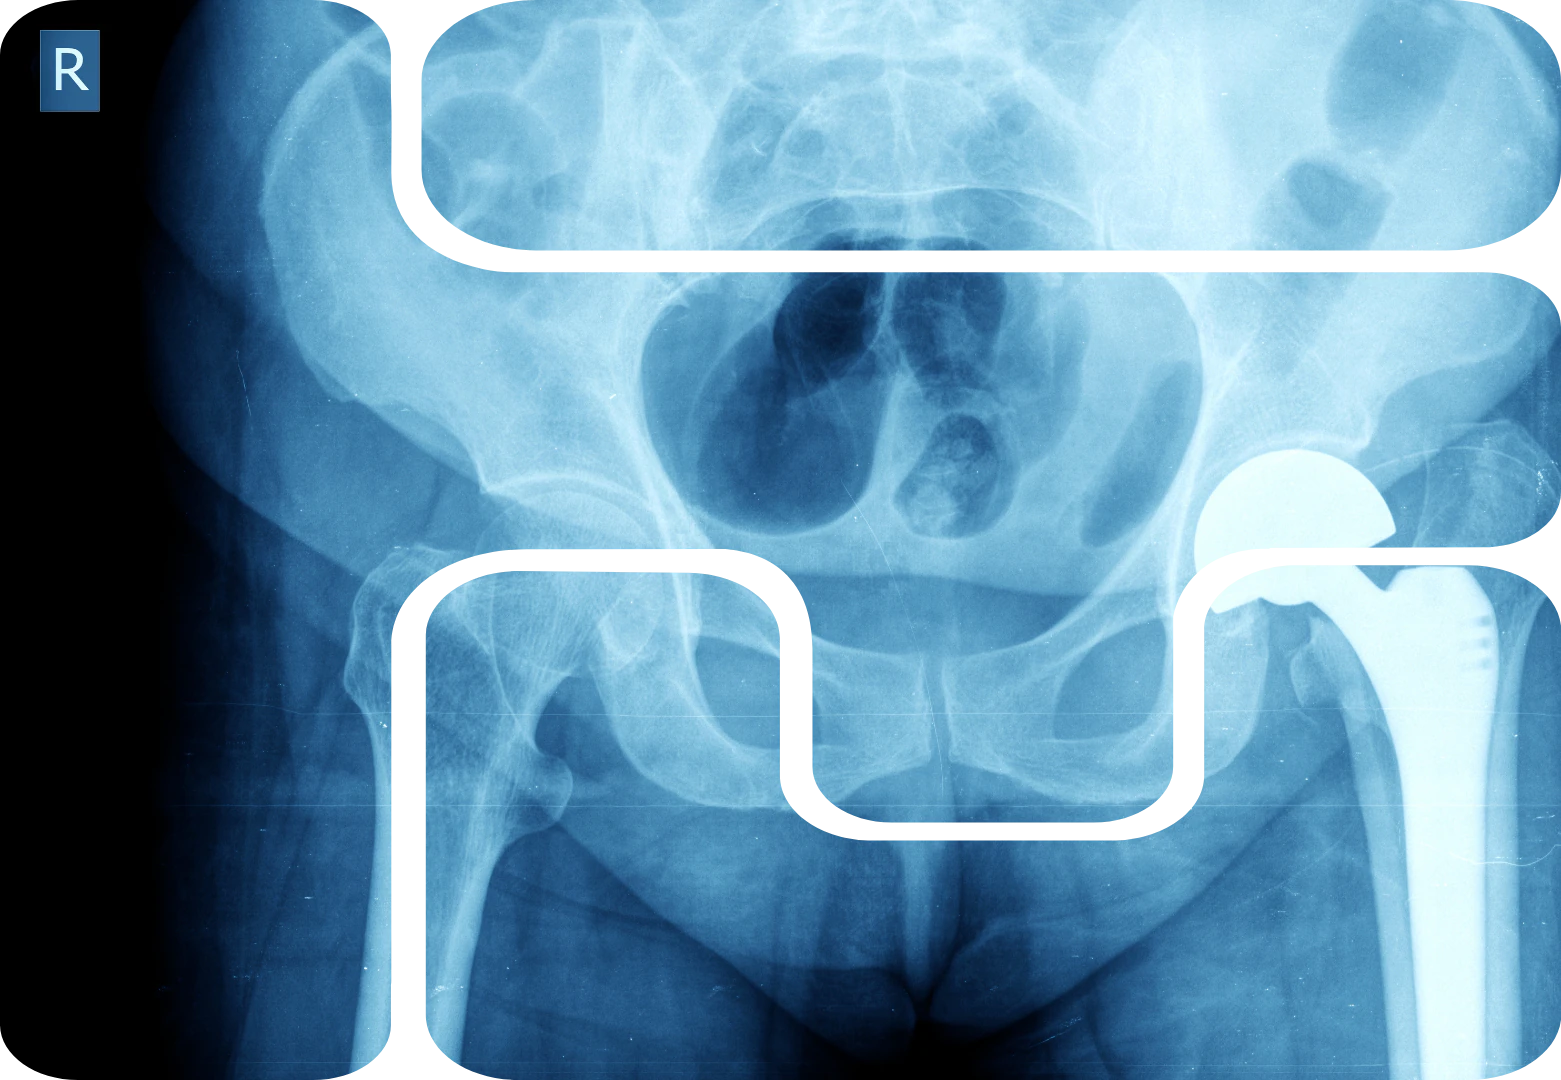

Für die Anfertigung dosisintensiver Aufnahmen (Abdomen, Hüfte, Becken, Schädel, Achsenskelett) ist eine anerkannte Strahlenschutz-Weiterbildung in erweiterter konventioneller Bildgebung (EKA) im mittleren Dosisbereich (MP8) erforderlich.

• Röntgenaufnahmen im mittleren Dosisbereich von Abdomen, Hüfte, Becken, Wirbelsäule und Schädel, Analyse und Interpretation der Röntgenbilder